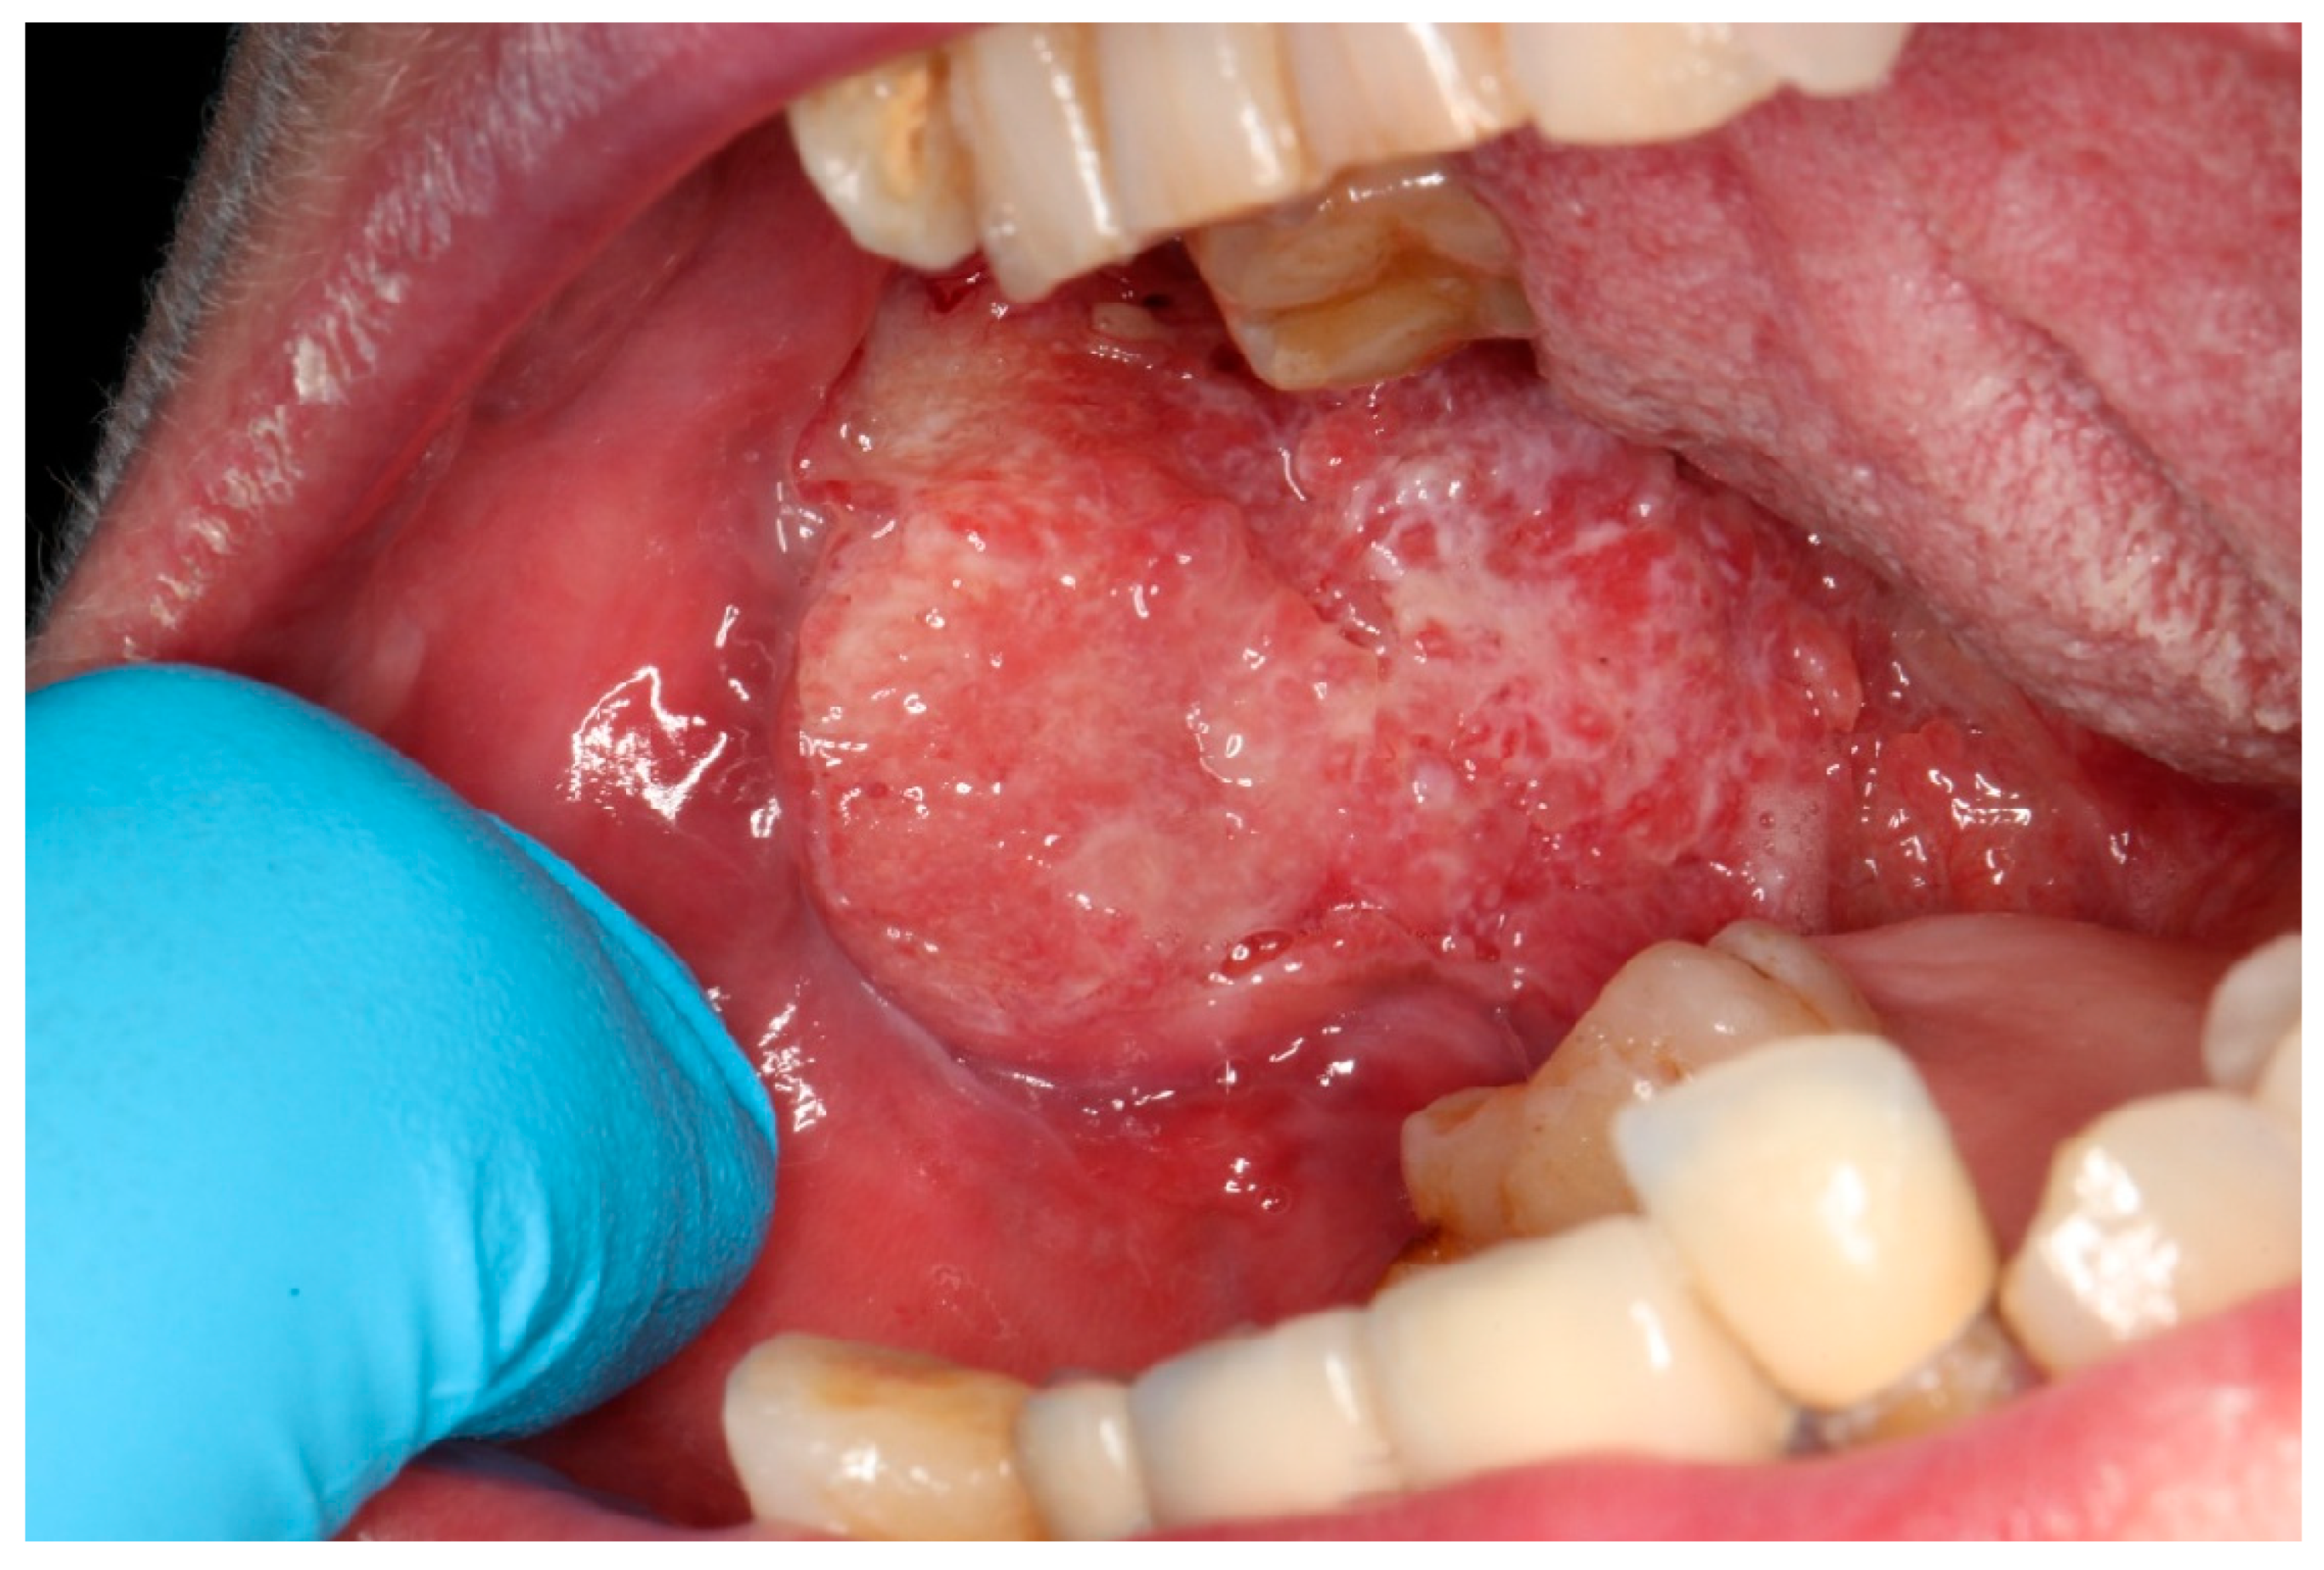

Oral squamous cell carcinoma (OSCC, Figure 1) is a heterogeneous cancer that develops from the mucosa lining of the oral cavity [1]. In 90% of oral cancer cases, patients are histologically diagnosed with OSCC [2], making it one of the most prevalent types of cancer in the oral cavity, accounting for 90% of head and neck squamous cell carcinoma (HNSCC) cases [1]. Data collected by the Global Cancer Observatory (GCO) show 389,846 new cases globally in 2022 for cancer of the lips or oral cavity, with 188,438 patient deaths. It is much more common in males, with incidence (268,999) and mortality (130,808) rates more than double compared to females (120,847 and 57,630, respectively). The age group with the highest number of new cases is 60–74 for females and 55–69 for males [3]. In Poland, the incidence of lip or oral cancer was 2239 in 2022, with 1437 patient deaths. The same tendencies were observed, with more than doubled incidence (1554) and mortality (1019) rates in males compared to females (685 and 418, respectively) [4].

Figure 1.

Advanced oral squamous cell carcinoma.